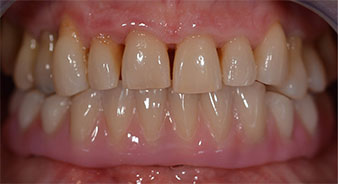

Una volta trascorso il tempo necessario per la osteointegrazione, è stato possibile prendere l'impronta definitiva degli impianti e, poi, è stata realizzata la protesi definitiva (Fig. 19 e 20). A questo punto, il dentista e la paziente hanno potuto decidere insieme se utilizzare delle faccette in ceramica o in vernice acrilica, con una struttura in zirconio o metallo. In questo caso, il Dott. Pascu e il suo team hanno preferito delle faccette in vernice acrilica, a seguito della prognosi difficile sulla dentatura mascellare e sulla posizione allungata del dente 24. Questo tipo di faccette è solitamente molto più facile da adattare e, di conseguenza, può essere modificato per rispondere alla nuova situazione della mascella.